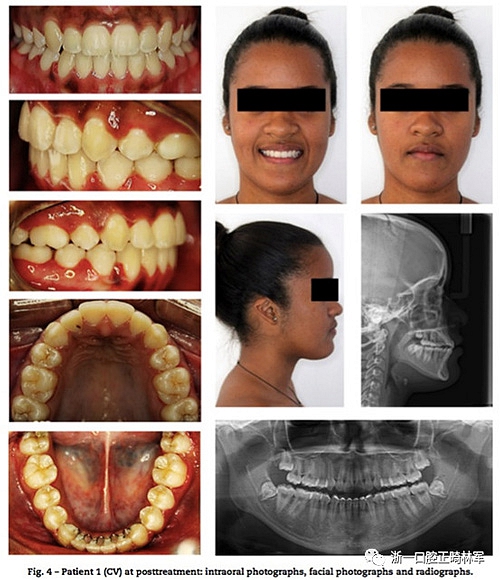

患者1使用0.022的Roth傳統(tǒng)矯治器。弓絲序列為0.014,0.016,0.018NiTi絲;0.018,0.02,及0.018×0.025的不銹鋼絲。治療初期拔除前磨牙,隨后在側切牙和尖牙間使用NiTi開口彈簧,間隙打開后側切牙上粘托槽,使用0.012NiTi,12月后牙排齊,關閉拔牙間隙,未使用支抗釘(圖3)。后12個月使用橡皮筋牽引直至矯治器移除,整個階段維持了24個月,期間每月復診(圖4)。

兩例下頜均使用3×3固定保持器,上頜使用改良Hawley保持器。在患者1和2治療過程比較顯示如圖6。頭影測量圖的疊加中證實了極大的相似性(圖7),治療前治療后和保持后的差異見圖8,9。